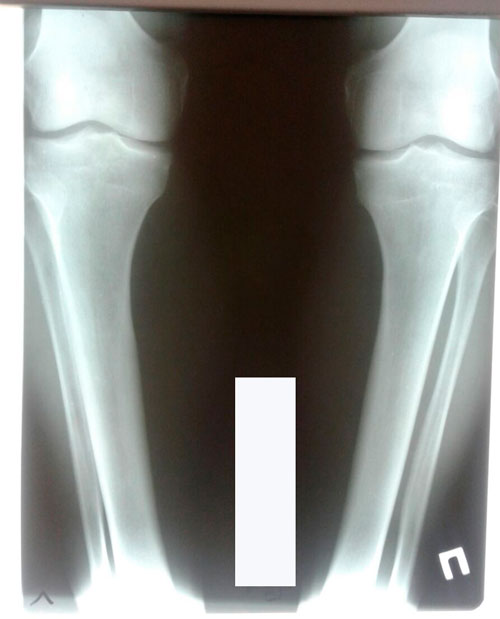

ножки на сращении

Дата операции 17.04.2018г.

Дата снятия аппаратов 18.07.2018г.

Срок сращения 90 дней.